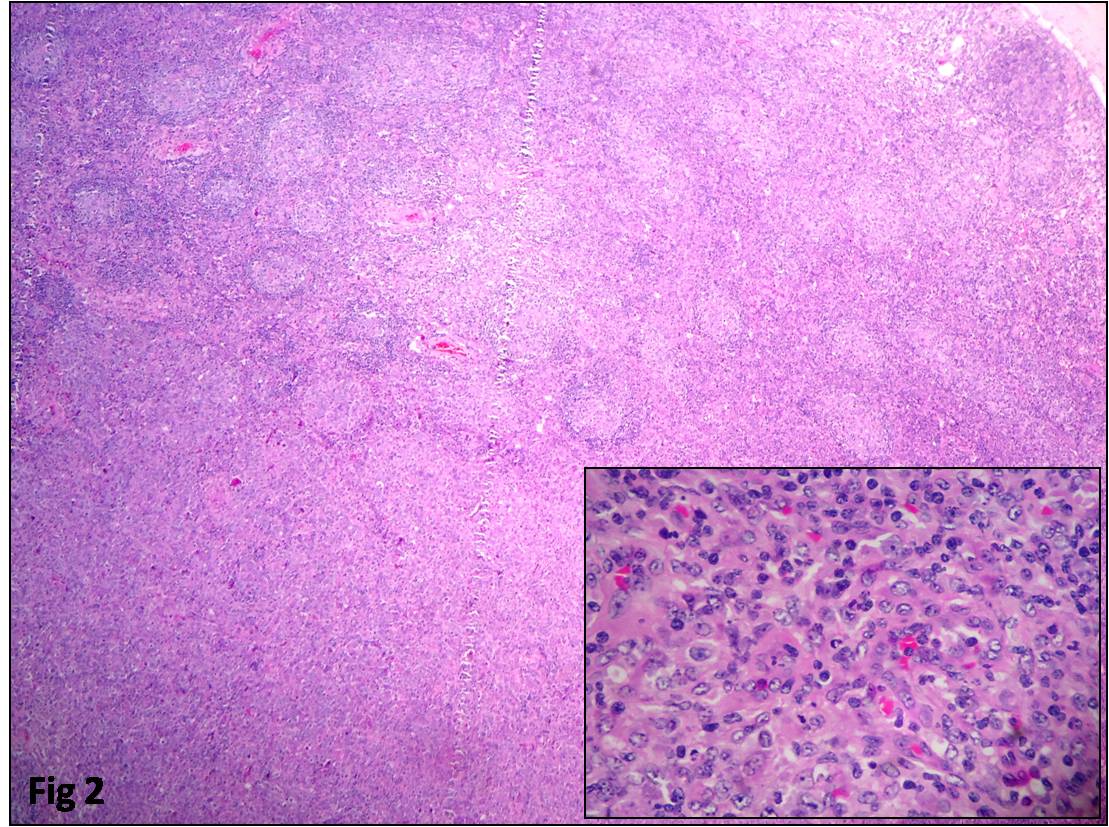

Follicular Lymphoma: A Clinicopathological Analysis from a Tertiary care Institute in Southern India